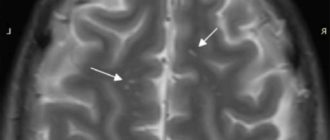

Мрт головного мозга глиоз или РС

Очаги глиоза в головном мозге в белом веществе (единичные) на МРТ: что это такое?